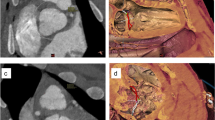

MRI, gross examination, and dissection of a CRISPR gene-edited SAP130 mutant term pig showed multiple malformations that consisted of an imperforated anus with rectal atresia (Fig. 7A–D), kidney defects when compared to normal age matched controls (Fig. 7E,F) including hypoplastic kidneys with one kidney showing very severe hydronephrosis with a thin rim of renal parenchyma and hydroureter and the other hypoplastic kidney showing a moderate hydroureter (Fig. 7G–J). In addition, this SAP130 piglet showed tricuspid valvar dysplasia, an atrial septal defect, and abnormal head and facies.

MRI and gross images of the malformations identified in a mutant SAP130 term pig. Image (A) shows the anal region showing the imperforate anus. Most of the tail has been removed. The in situ gross image of the abdomen shows the distended colon (B). A sagittal MRI (C) shows the distended colon and rectum and the site of the atresia, and (D) is the gross dissection of the atretic rectum. Image (E) is an MRI of normal (wild type) kidneys and (F) shows the gross appearance of normal pig kidneys. Illustration (G) is the cut surface of hypoplastic kidney found in the mutant pig. An MRI of the mutant pig kidneys (H) shows one hypoplastic kidney and one hypoplastic kidney with severe hydronephrosis with a hydroureter. Image (I) shows the gross appearance of the hypoplastic kidneys with the one kidney showing hydronephrosis with a hydroureter. The opened hypoplastic and hydronephrotic kidney of the mutant (J) showing the severe hydronephrosis with the loss of renal architecture with only a narrow rim of renal parenchyma identified. IA-Imperforate anus, SC-Spiral colon, ICV-Inferior caval vein, Kid-Kidney, Uret-Ureter, RP-Renal parenchyma.